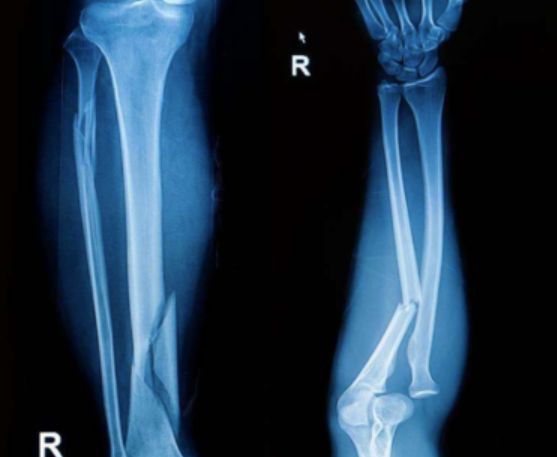

2、X线检查.X线变化在感染后3~4周出现,表现为骨质不规则增厚和硬化,有残留的骨吸收区或空洞,其中可有大小不等的死骨,有时看不到骨髓腔。

3、CT检查若X线表现不明确,可行CT检查以确定病变骨及显示椎旁脓肿的形成,放射骨扫描在病变早期即有反映,但无法区别感染。